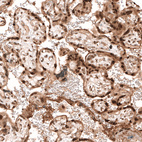

Immunohistochemical staining of human placenta shows strong nuclear positivity in trophoblastic cells.